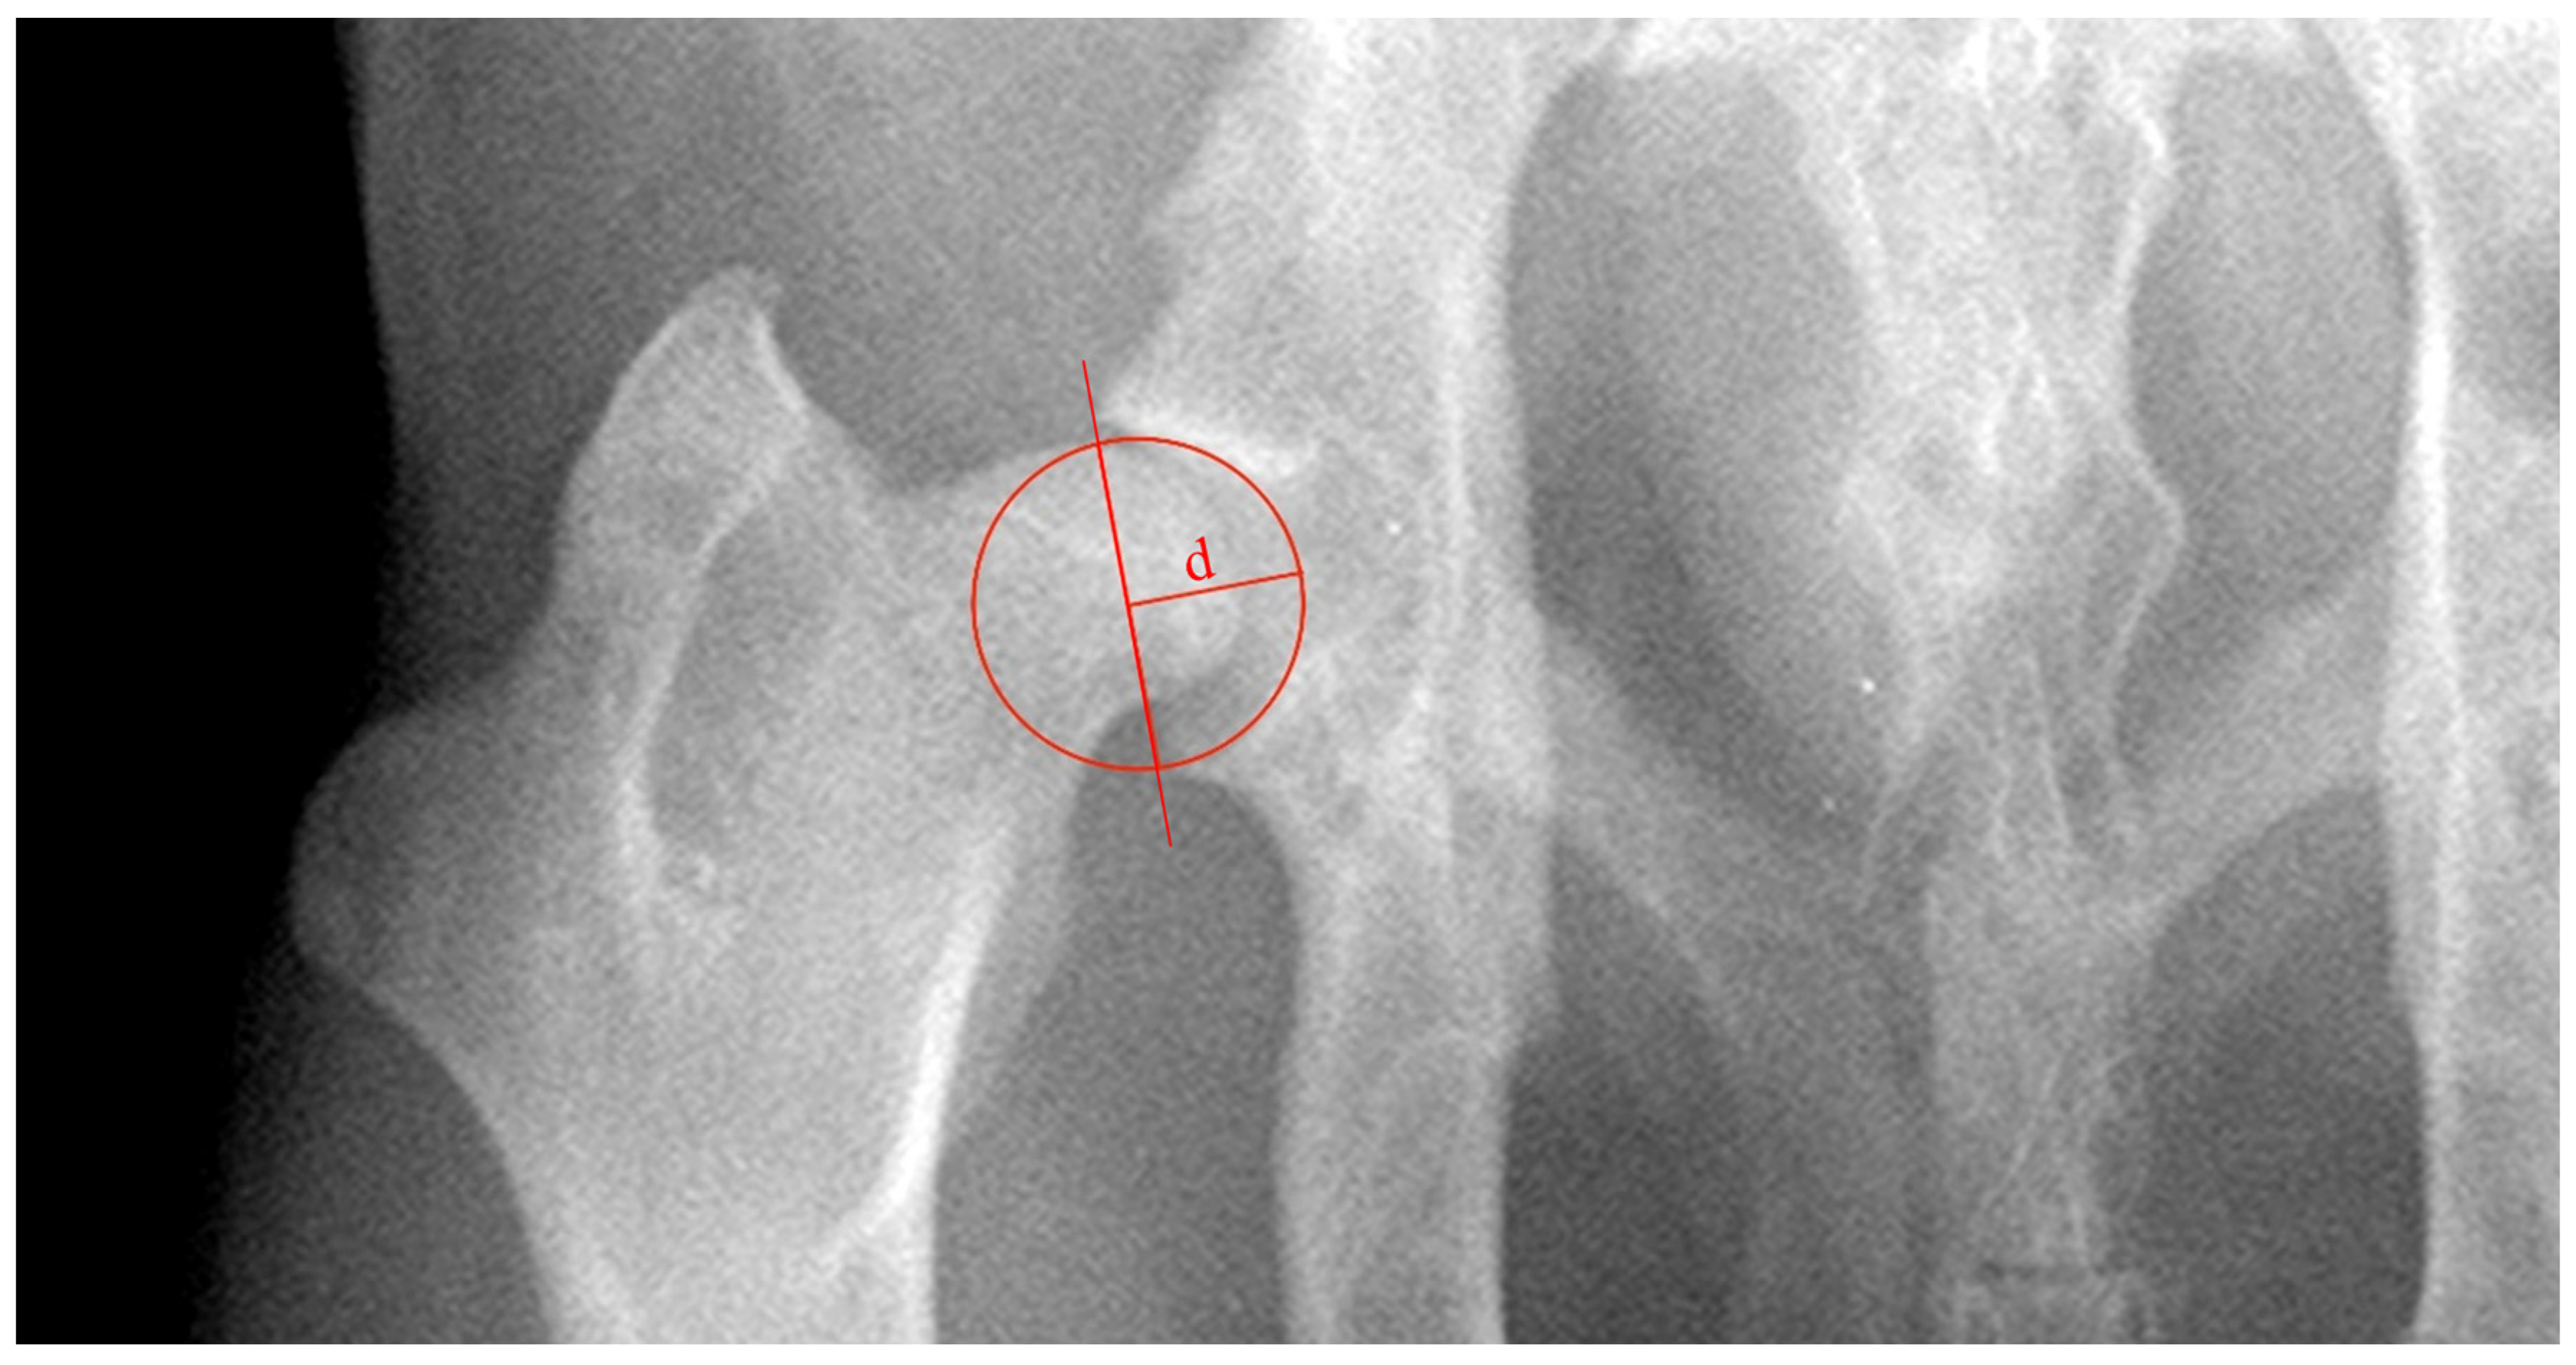

ADi_xR was evaluated as the ratio between ‘d’, the acetabular depth, and the acetabular diameter (d/Ø, in mm) (Figure 3). Distance ‘d’ was defined as the biggest perpendicular distance concerning the line tangent to the craniolateral and caudal acetabular edges [12].

Figure 3. Ventrodorsal radiograph of the hip joint illustrating the methodology used to evaluate the acetabular depth index (ADi_xR). ADi_xR was evaluated as the ratio between ‘d’, the acetabular depth, and the acetabular diameter. Distance ‘d’ was defined as the biggest perpendicular distance concerning the line tangent to the craniolateral and caudal acetabular edges.